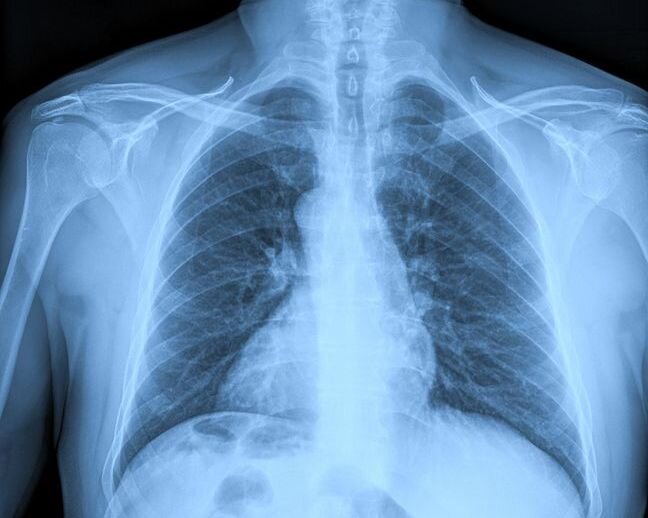

Successful Metrology Partnership project workshop on X-ray imaging dosimetry

Medical X-ray

Providing the metrology required to ensure patient safety during medical X-rays

Metrology Partnership project Traceability in medical X-ray imaging dosimetry (22NRM01, TraMeXI) is working to review a range of radiation conditions relevant in medical imaging and produce a proposal to update the procedures used for dosimeter calibrations and clinical measurements.